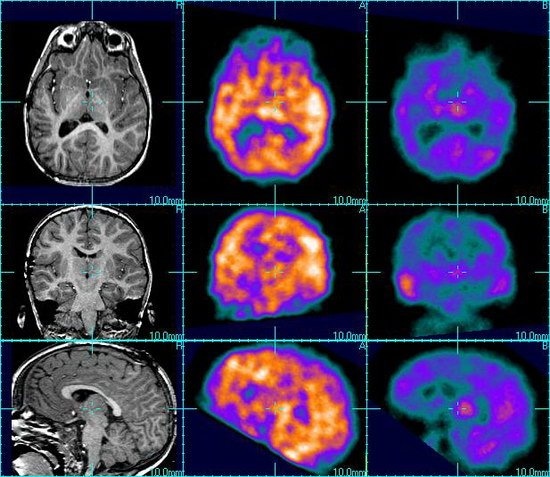

Но Австралийские ученые нашли способ обнаружения и предсказания припадков. Они провели эксперимент, вживив в голову пятнадцати больных специальный имплантант. Он реагировал на изменение активности в определенных участках мозга, которые активизируются при появлении припадков. В итоге информация передавалась на устройство, которое вычисляет вероятность возникновения припадка.